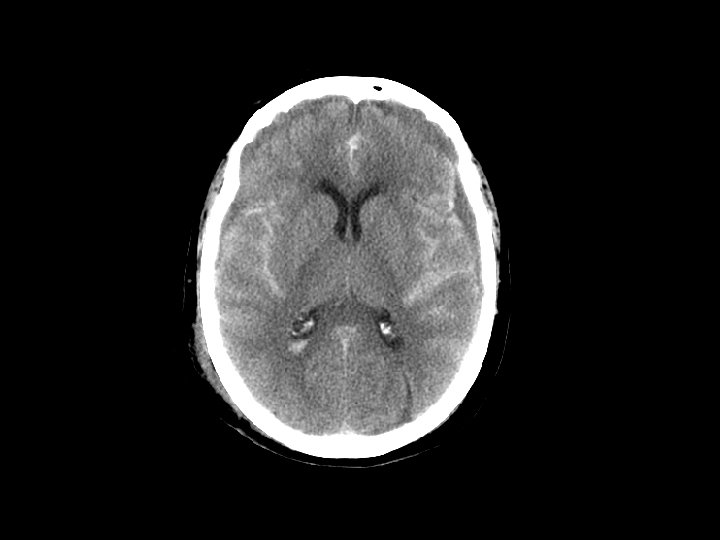

Subarrachnoid Hemorrhage (SAH) • SAH and contusion are most common injuries on CT after blunt trauma • CT: blood in the sulci and basal cisterns • Often associated with intracranial hematomas • Must consider that the SAH caused the trauma (spontaneous bleed and then fall) • Complications: – Arterial vasospasm: 2 -3 days after injury